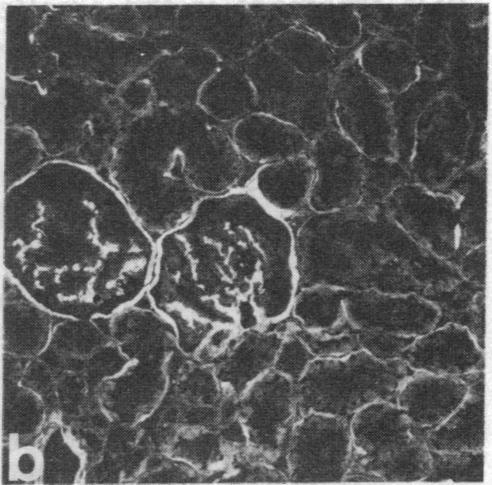

Monoclonal antibodies (mAbs) have been prepared against type IV collagen isolated from human kidney. Two mAbs, designated CIV 22 and CIV 16, were extensively characterized. CIV 22 reacted only with native type IV collagen, whereas CIV 16 also bound to fragments derived from the alpha 1(IV) chain after reduction and alkylation of the molecule. Therefore, CIV 22 recognizes a conformational epitope on the triple helical type IV collagen, whereas CIV 16 binds to a sequential determinant in the carboxyl-terminal half of the alpha 1(IV) chain. By immunofluorescence, typical basement membrane structures were stained with both mAbs on frozen sections of different human organs. The mAbs were used to investigate the chain composition of type IV collagen. Radiolabeled type IV collagen bound to CIV 22, proving its triple helical configuration. These native probes, containing both the alpha 1(IV) and the alpha 2(IV) chains, also bound to CIV 16. Since CIV 16 does not react with the isolated alpha 2(IV) chain, both chains must be arranged in a single triple helical molecule (heterotrimer).

已制备出针对从人肾中分离出的IV型胶原的单克隆抗体(mAb)。对两种单克隆抗体,即CIV 22和CIV 16进行了广泛的特性分析。CIV 22仅与天然IV型胶原反应,而CIV 16在分子还原和烷基化后也与源自α1(IV)链的片段结合。因此,CIV 22识别三螺旋IV型胶原上的构象表位,而CIV 16结合α1(IV)链羧基末端一半中的连续决定簇。通过免疫荧光法,在不同人体器官的冰冻切片上,两种单克隆抗体均对典型的基底膜结构进行了染色。这些单克隆抗体被用于研究IV型胶原的链组成。与CIV 22结合的放射性标记IV型胶原,证明了其具有三螺旋结构。这些包含α1(IV)链和α2(IV)链的天然探针也与CIV 16结合。由于CIV 16不与分离出的α2(IV)链反应,两条链必定排列在单个三螺旋分子(异源三聚体)中。